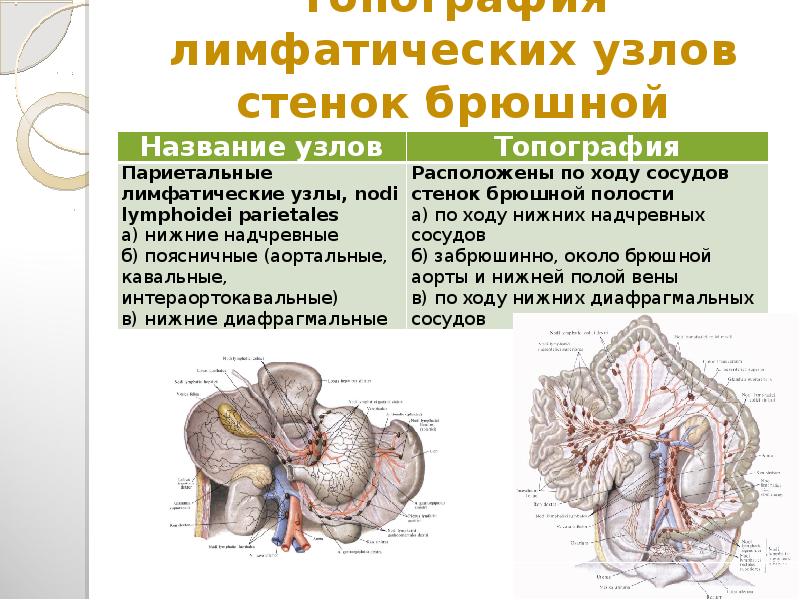

Мезентериальные лимфатические узлы: УЗИ и диагностика